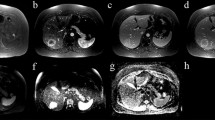

H&E-stained histological images showed a significant difference in tumor cell viability between four treatment groups (Fig. 5A–D). All treatment groups—NK cell infusion, sorafenib, and their combination—substantially reduced tumor cell counts compared to the control (p < 0.05), with the combination therapy proving more effective than either treatment alone (p < 0.05). Notably, there was no significant difference in tumor cell reduction between the NK cell infusion and sorafenib groups, suggesting comparable efficacy. A multivariable analysis of these H&E-stained sections identified five key features, which informed the construction of regression models associated with tumor cell count. The T1w MRI model showcased an RMSE of 0.09 and a correlation coefficient of 0.92. The T2w MRI model achieved an RMSE of 0.04 and a correlation coefficient of 0.91, while the T1w + T2w MRI model yielded an RMSE of 0.05 with a correlation coefficient of 0.90 (Fig. 5I).

Histological Analysis of HCC Treatments with H&E and CD56 Staining. Arrow shows the tumor cell (dark pink) and NK cell (dark brown). A–D H&E-stained histological sections revealing the tumor cell viability for the (A) control group, (B) sorafenib treatment, (C) NK cell IHA treatment and (D) combination therapy. E–H CD56-stained sections highlighting NK cell activity for the (E) control group, (F) sorafenib treatment, (G) NK cell IHA treatment, and (H) combination therapy. I, J Correlation curves between MRI features and both (I) H&E and (J) CD56 histological biomarkers

Inspection of CD56+-stained histological images discerned a significant variation in NK cell activity across the same four treatment groups (Fig. 5E–H). An increased presence of NK cells was significantly observed in the combination therapy group compared to the single-treatment and control groups (p < 0.05). Furthermore, NK cell immunotherapy induced a more pronounced NK cell migration compared to sorafenib treatment (p < 0.05), with both groups exhibiting a significant increase in NK cells relative to the control group (p < 0.05). For the CD56+ multivariable analysis, the models based on five chosen features, reported RMSE values of 0.05, 0.04, and 0.03 for T1w, T2w, and T1w + T2w MRI datasets, respectively, with corresponding correlation coefficients of 0.89, 0.92, and 0.94 (Fig. 5J).